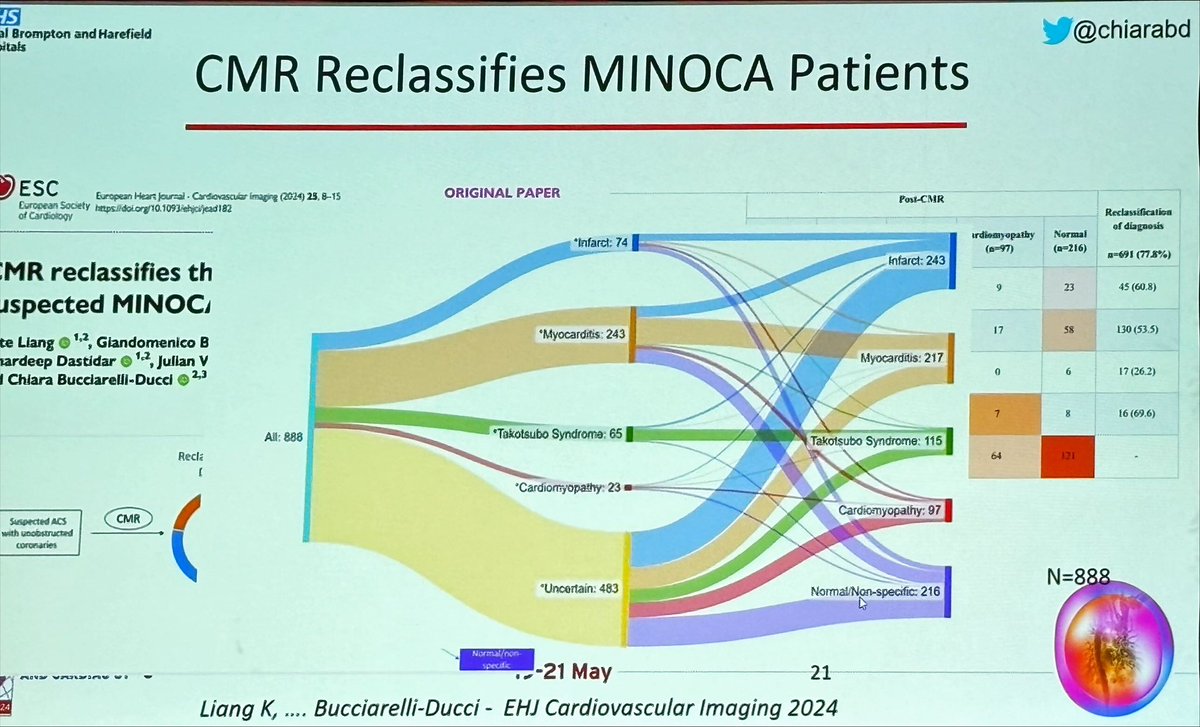

Great pleasure to listen to the fantastic C Bucciarelli-Ducci talking about MINOCA #ICNCCT2024

#ICNCCT2024 #CMR reclassifies diagnosis of MINOCA C Bucciarelli-Ducci shows the value of the modality